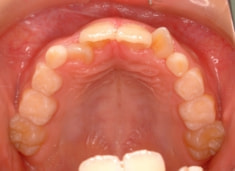

治療法:上顎急速拡大装置+クリアスナップ+フェイスマスク+上顎3番は開窓牽引CT写真にて位置確認